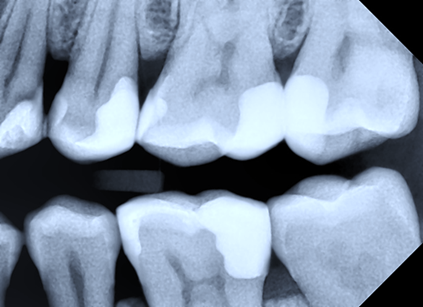

Subsequently, the interdental contact was analyzed by evaluating its presence or absence (Fig. 4), as well as its positioning in the cervico-occlusal direction, with the establishment of anatomical or non-anatomical localization.

|

Fig. 4 Bitewing radiography. Proximal restorations with the absence of interdental contact between teeth 25-26, 35-36. |